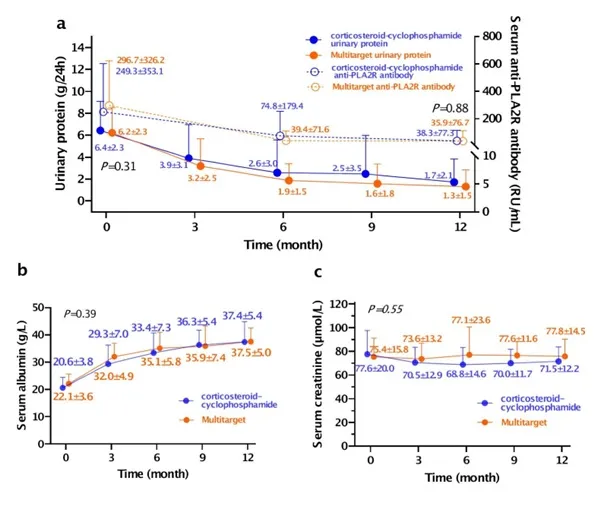

O desfecho primário de remissão completa ou parcial em 12 meses foi alcançado em 31/39 pacientes (79%) no grupo de terapia multitarget e 34/39 (87%) no grupo Ponticelli (RR 0,93; IC 95% 0,72– 1,21; P = 0,85), figura 1A.

A remissão completa em 12 meses foi alcançada por 16 pacientes (41%) no grupo de terapia multitarget e 14 (36%) no grupo corticosteróide-ciclofosfamida, figura 1B.

A proteinúria e as concentrações séricas de anticorpo anti-PLA2R diminuíram e a concentração sérica de albumina aumentou gradualmente em ambos os grupos durante o acompanhamento. Não houve diferenças significativas nas alterações na proteinúria, concentrações séricas de anticorpo anti-PLA2R ou concentrações de albumina entre os dois grupos (P = 0,31, 0,88 e 0,39, respectivamente, usando modelos lineares generalizados).